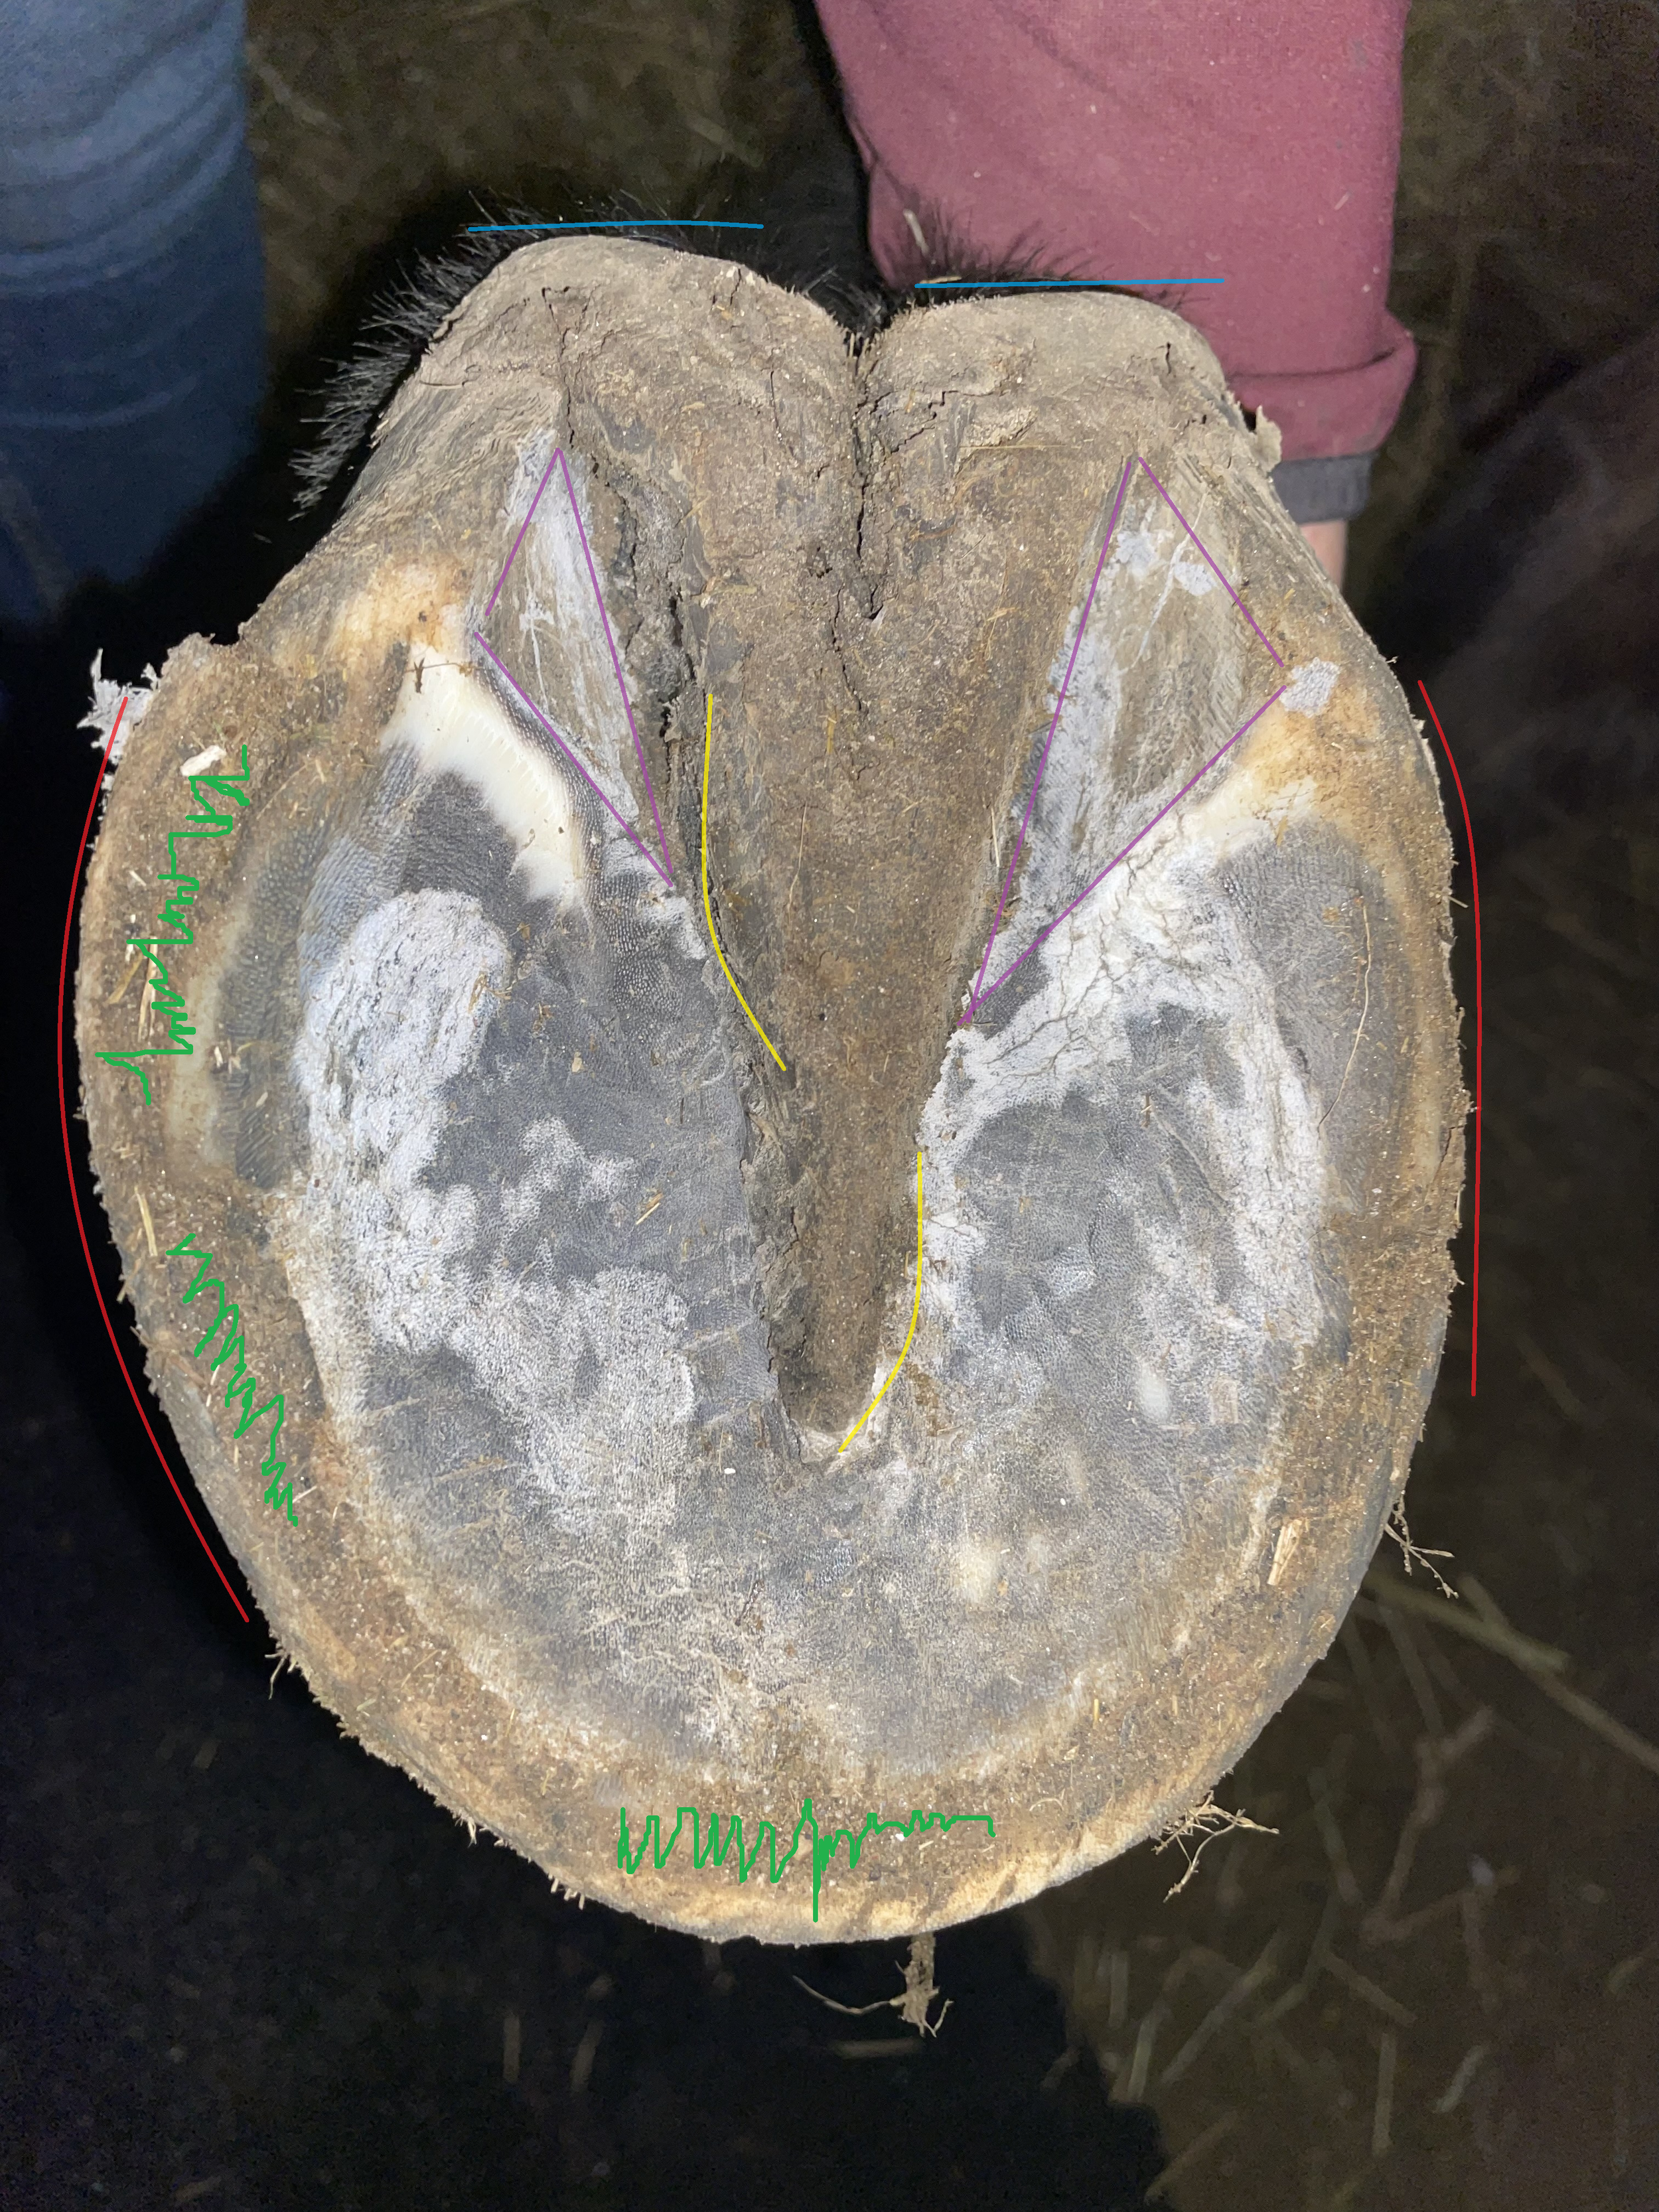

Die huforthopädische Behandlung von Barhufen hat zum Ziel, für jedes Pferd das individuell bestmögliche Optimum des Hufes zu erarbeiten. Dabei geht es nicht um starre Ideale, sondern um eine funktionelle, physiologische Hufform, die eine ausbalancierte Lastaufnahme ermöglicht und den gesamten Bewegungsapparat unterstützt.

Fehlstellungen werden behutsam korrigiert – immer im Rahmen dessen, was für das jeweilige Pferd sinnvoll und umsetzbar ist.

Um den Bewegungsapparat nachhaltig positiv zu beeinflussen, betrachte ich jedes Pferd ganzheitlich. In meine Arbeit fließen unter anderem Alter, Gesundheitszustand, mögliche Vorerkrankungen, Haltungsform, Bewegungsumfang sowie die individuellen Ziele ein, die mit der huforthopädischen Behandlung erreicht werden sollen.

✅ Du erhältst ein persönliches Berichtsheft mit Fotodokumentation, um die Hufentwicklung transparent nachzuvollziehen.

In dieser kompakten Beratung schauen wir gemeinsam auf die Hufe deines Pferdes. Ziel ist es, dir Klarheit und Orientierung zu geben: Wo stehen die Hufe aktuell, wo gibt es Verbesserungspotenzial und wie könnten die nächsten sinnvollen Schritte aussehen.

✅ Ob und in welchen Bereichen die Hufe deines Pferdes verbessert werden sollten

✅ Welche Veränderungen grundsätzlich möglich und sinnvoll wären